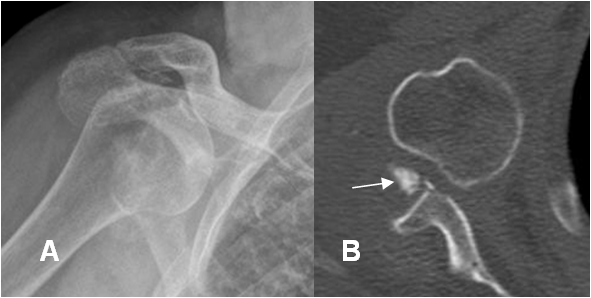

Fig 45 B. Luxación anterior.

A: Rx AP. Luxación glenohumeral anterior.

B: TAC axial. Se confirma la luxación. Adicionalmente hay un fragmento libre intra-articular.